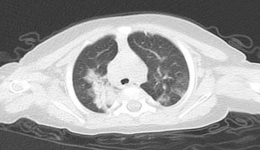

近日,桃溪院區新引入一臺西門子雙源CT(SOMATOMDefinitionFlash炫速雙源CT),雙源CT技術領先,性能卓越,是目前全球領先的CT設備之一,其核心技術在于雙源結構設計,配備兩套X射線球管和探測器系統。這種設計使得該設備能夠在很短的時間內完成高...